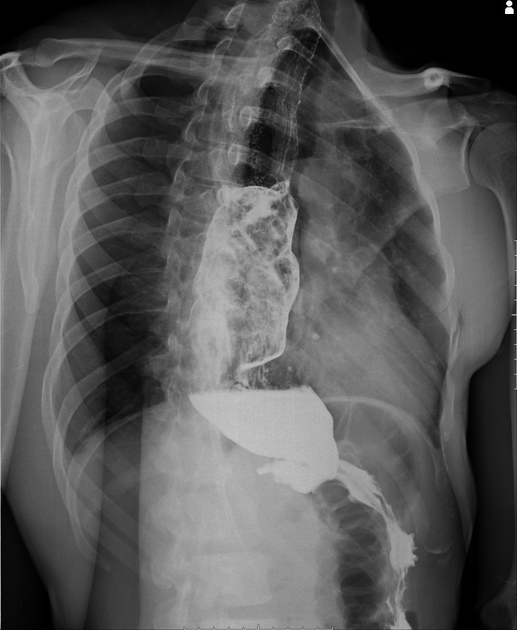

Para mais, os exames recomendados para a avaliação inicial do paciente com doença de Chagas na forma crônica são o eletrocardiograma (ECG) - ao menos uma vez ao ano - e o raio-X de tórax. Caso o ECG apresenta alterações, deve-se realizar o ecocardiograma.

Além disso, em casos suspeitos de megacólon chagásico, realiza-se o exame enema opaco. E em caso de suspeita de megaesôfago, a radiografia contrastada do órgão. Em caso de suspeita de megaescófago chagásico, realiza-se a radiografia com bário para observar a progressão do contraste, bem como observar distúrbios de motilidade característicos da doença.